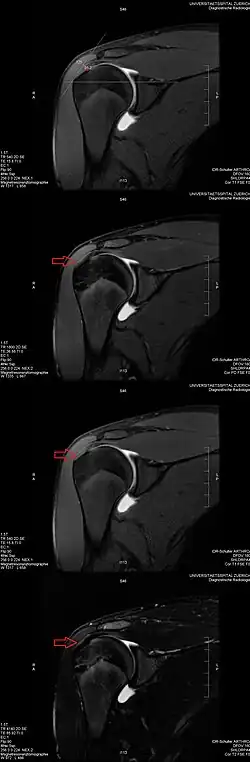

Magic angle effect seen on MRI of the shoulder

Application to medical imaging: The magic angle artifact

The magic angle artifact refers to the increased signal observed when MRI sequences with short echo time (TE) (e.g., T1 or proton density spin-echo sequences) are used to image tissues with well-ordered collagen fibers in one direction (e.g., tendon or articular hyaline cartilage).[1] This artifact occurs when the angle such fibers make with the magnetic field is equal to θm.

Example: This artifact comes into play when evaluating the rotator cuff tendons of the shoulder. The magic angle effect can create the appearance of supraspinatus tendinitis.